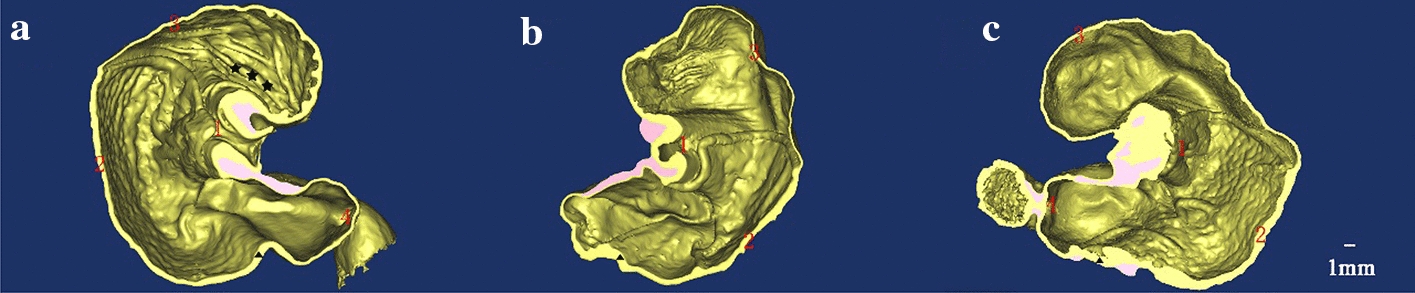

Three-dimensional reconstruction images of the same rats’ gastric specimens

To further reconfirm the advantage of the XILPCI 3-dimensional images, we reconstructed 3-dimensional images of the different stages of the stomach as shown in Fig. 6. The XILPCI 3-dimensional images show a clear structure of the interior stomach (showed as Additional file 1: Video S1), and we could see the clear images of the villus of the fundus in the young rat stomach. There is a clear demarcation line between the gastric fundus and corpus. The wall of the 12-week-old rat stomach is thicker than those of the 4-week-old. The conclusion here shows that XILPCI has a high anatomical accuracy for stomachs images. In addition, the thickness of the gastric wall at various stages was measured in Fig. 6 to compare the thickness of gastric specimens. As shown in Fig. 7, the results indicate that the average value of gastric wall at the same stage is very similar, and the measurement of gastric wall by 3-dimensional images in Fig. 6 has certain reference significance. Just as shown in Fig. 7a, the thickness of 4-week-old gastric wall for the right panel is lower than that of the left one, but the thickness of 6-week-old gastric wall is higher for the right panel, probably because of the randomness of specimen selection and the existence of measurement error. To further confirm the experimental evidence, we measured the thickness of gastric wall of the dried specimens which can be directly used for XILPCI experiments. As the Fig. 7b shown, it is clearly indicated the different types of gastric specimens shrink proportionally. However, these results are also in line with the requirements of statistics and within a reasonable range.

Fig. 6.

3D anatomical structure images of the coronal plane of different stages of the stomach. a 3D internal structure image of the 4-week-old rat stomach. The stomach is round with obvious wrinkles in the fundus part, and there is a clear demarcation line between the gastric fundus and gastric corpus. b 3-dimensional internal structure image of the 6-week-old rat stomach. The wrinkles of the fundus part are decreasing, and the gastric corpus is becoming rugged. c 3-dimensional internal structure image of the 12-week-old rat stomach. The stomach is elliptic, and the fundus part of it has become smooth. ★★★ represents the wrinkles of the gastric fundus. ▲ is the same size in the a, b and c part of Fig. 6 and represents the thickness of the wall of the gastric corpus. 1 Cardia, 2 Gastric Corpus, 3 Gastric Fundus, 4 Pylorus